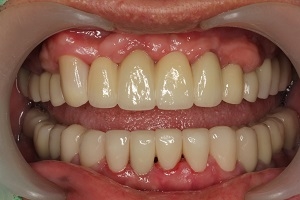

1. 經由多顆人工植牙及全瓷假牙的全口重建,牙周病治療讓病人恢復咬合的功能與美觀,也易於每日的清潔保養。

治療後

人工植牙與全口治療